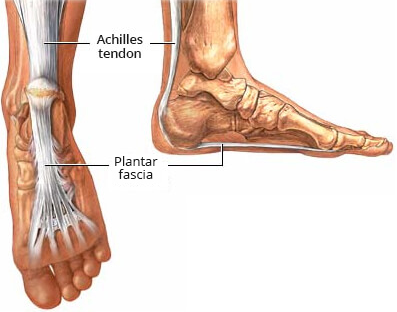

Plantar fasciitis and achilles pain clearance

Plantar fasciitis and achilles pain clearance, Is My Heel Pain Achilles Tendonitis vs Plantar Fasciitis Ease Achilles Heel Pain With These Tips clearance

Plantar fasciitis and achilles pain clearance

Achilles Tendonitis vs. Plantar Fasciitis Which Do I Have Arlington Mansfield Foot Ankle Centers Podiatrists clearance, plantar fasciitis clearance, Heel Pain Causes and Treatment clearance, Achilles Tendon Pain and Plantar Fasciitis Treatment Guide clearance, This Stretch Relieves Plantar Fasciitis Shin Splints Achilles Pain and Heel Pain Focusphysiotherapy clearance, Heel Pain Plantar Fasciitis Delaware Foot and Ankle Group Podiatrist in Newark DE clearance, Plantar Fasciitis and Achilles Tendonopathy InterX Pain Clinic Stratford Upon Avon clearance, Heel Pain Podiatrist Temple Hill Clinton MD Burton J. Katzen DPM clearance, Back of Achilles Tendon Heel Pain Shoes Orthotics Home Treatment clearance, Seattle Bellevue Heel Pain Center Issaquah Foot Ankle Specialists clearance, Interwoven Threads The Plantar Fascia Achilles Tendon Connection clearance, Plantar fasciitis VS Achilles tendinitis Managing Heel Pain Greg Robinson Ibraheem Podiatry clearance, Can Plantar Fasciitis Cause Calf Pain clearance, Plantar fasciitis achilles tendon deals pain clearance, On the morphological relations of the Achilles tendon and plantar fascia via the calcaneus a cadaveric study Scientific Reports clearance, This One Stretch Helps Relieve Plantar Fasciitis Shin Splints Achilles Pain and Heel Pain clearance, Plantar Fasciitis Symptoms and Treatment Doctor clearance, Effective Treatment for Heel Pain Foot Foundation clearance, Plantar Fasciitis Chiropractors in Newmarket ON clearance, Plantar Fasciitis FAQ s clearance, Plantar Fasciitis Symptoms Causes Treatment Options clearance, Is My Heel Pain Achilles Tendonitis vs Plantar Fasciitis Ease Achilles Heel Pain With These Tips clearance, Plantar fasciitis Information Mount Sinai New York clearance, Achilles Tendonitis Plantar Fasciitis clearance, Common Problems that Can Lead to Plantar Fasciitis and Achilles Tendonitis clearance, Heel Pain clearance, Is Plantar Fasciitis Your Achilles Heel Prosper clearance, Plantar Fasciitis Dr7 Physiotherapy Podiatry Hydrotherapy Massage clearance, Foot or Heel Pain It Might Be Plantar Fasciitis Healthy You clearance, Achilles Tendonitis and Plantar Fasciitis Premier Podiatry Velimir Petkov DPM Podiatrists clearance, Achilles Tendonitis Vs Plantar Fasciitis Which Do I Have clearance, Difference between Plantar Fasciitis and Achilles Tendonitis Achieve clearance, Achilles Tendonitis vs. Plantar Fasciitis clearance, Achilles tendonitis vs. plantar fasciitis How to tell the difference clearance, Achilles tendonitis vs. plantar fasciitis How to tell the difference clearance, Product Info: Plantar fasciitis and achilles pain clearance.

Plantar fasciitis and achilles pain clearance

Plantar Fasciitis Symptoms and Treatment Doctor- plantar fasciitis and achilles pain